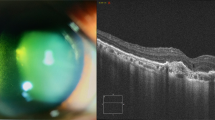

IVT, AC, i.c. and ICM injection